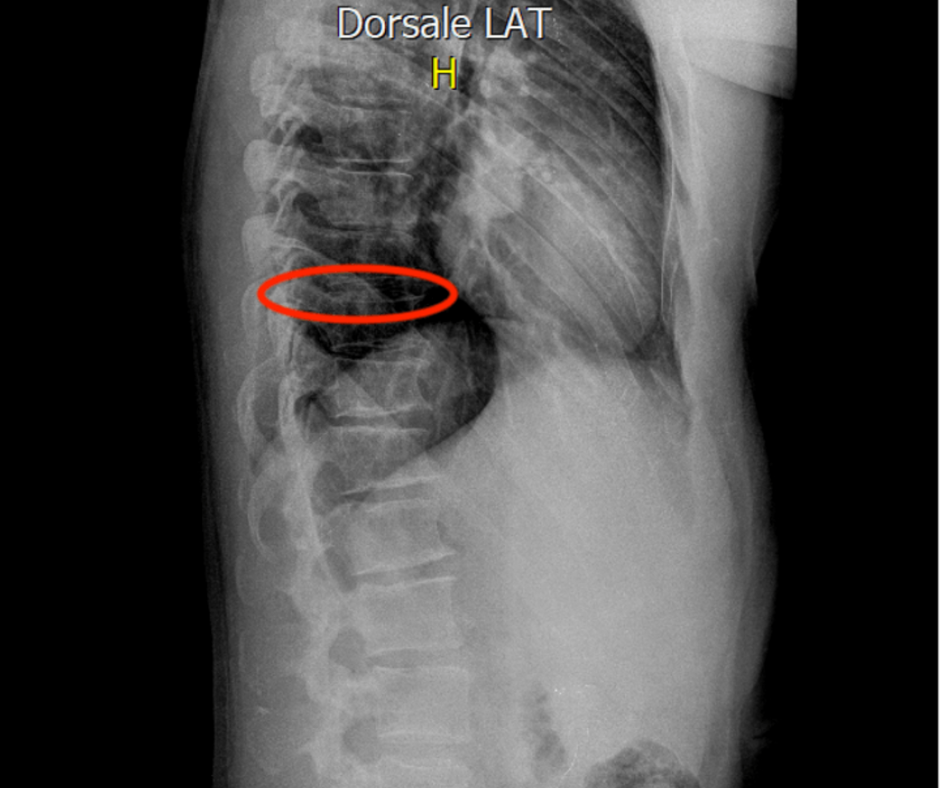

Figura 1 RX postumi frattura D9 limitante somatica superiore

Anamnesi: Paziente con esiti di frattura vertebrale di D9 traumatica per caduta in motocicletta. Si presenta in studio a 5 mesi dall'evento con permanenza del dolore zona dorso-lombare e lombare fino a cresta iliaca dx, presentando inoltre limitazione funzionale nei movimenti del tronco e paura a svolgere movimenti. Dai controlli radiografici e dalla visita ortopedica la frattura risulta totalmente consolidata persiste però il dolore e la limitazione funzionale.